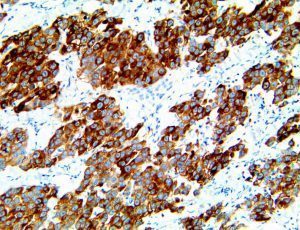

The first cytokines released are interleukin 1β (IL-1β) and tumor necrosis factor-α (TNF-α), which attract a variety of circulating white blood cells (WBCs) to the infection site, including neutrophils, monocytes, macrophages, and natural killer (NK) cells. This response, along with the antipathogenic chemicals released by these cells (i.e., complement), comprise the innate immune response. These cells directly attack the invading pathogen and also release additional cytokines, chief among them interleukin-1 and 6 (IL-6). IL-6 is essential for invoking the adaptive immune response, which calls T-cells, B-cells, and T helper (Th) cells to the infection site. IL-6 also stimulates further recruitment, proliferation and activation of macrophages.

It is the ICU physician who is most likely to witness one of the deadliest manifestations of the abnormal immunological response, the cytokine storm syndrome (CSS). This response is also referred to by some as the cytokine release syndrome (CRS). CSS is characterized by continuous activation and expansion of macrophage and lymphocyte populations, which secrete large amounts of cytokines, causing the cytokine storm. This massive cytokine release is akin to hemophagocytic lymphohistiocytosis (HLH) disease, a syndrome characterized by initial unchecked and persistent activation of cytotoxic T lymphocytes and NK cells.

This activation induces inflammatory monocytes to highly express IL-6, starting a localized and then systemic cascade effect that results in hyperproduction of IL-6, which accelerates the inflammatory process. Because IL-6 also increases vascular permeability, excessive levels cause blood vessels to become very leaky. This, along with clotting factors released from vascular endothelial cells, stimulates the coagulation cascade, resulting in microthrombosis (tiny clots), which leads to ischemia and tissue death of the kidney, intestines, heart, liver, brain and extremities.